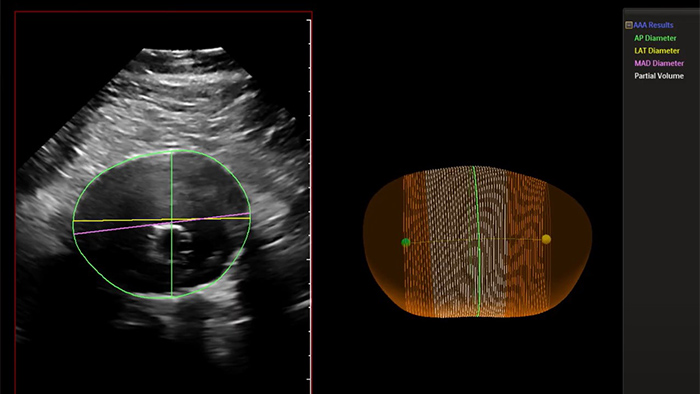

Philips Abdominal Aortic Aneurysm Model

Philips AAA Model is a software application that helps clinicians detect, segment and quantify 3D ultrasound data for use in surveillance of native and post-endovascular aneurysm repair (EVAR) AAAs.